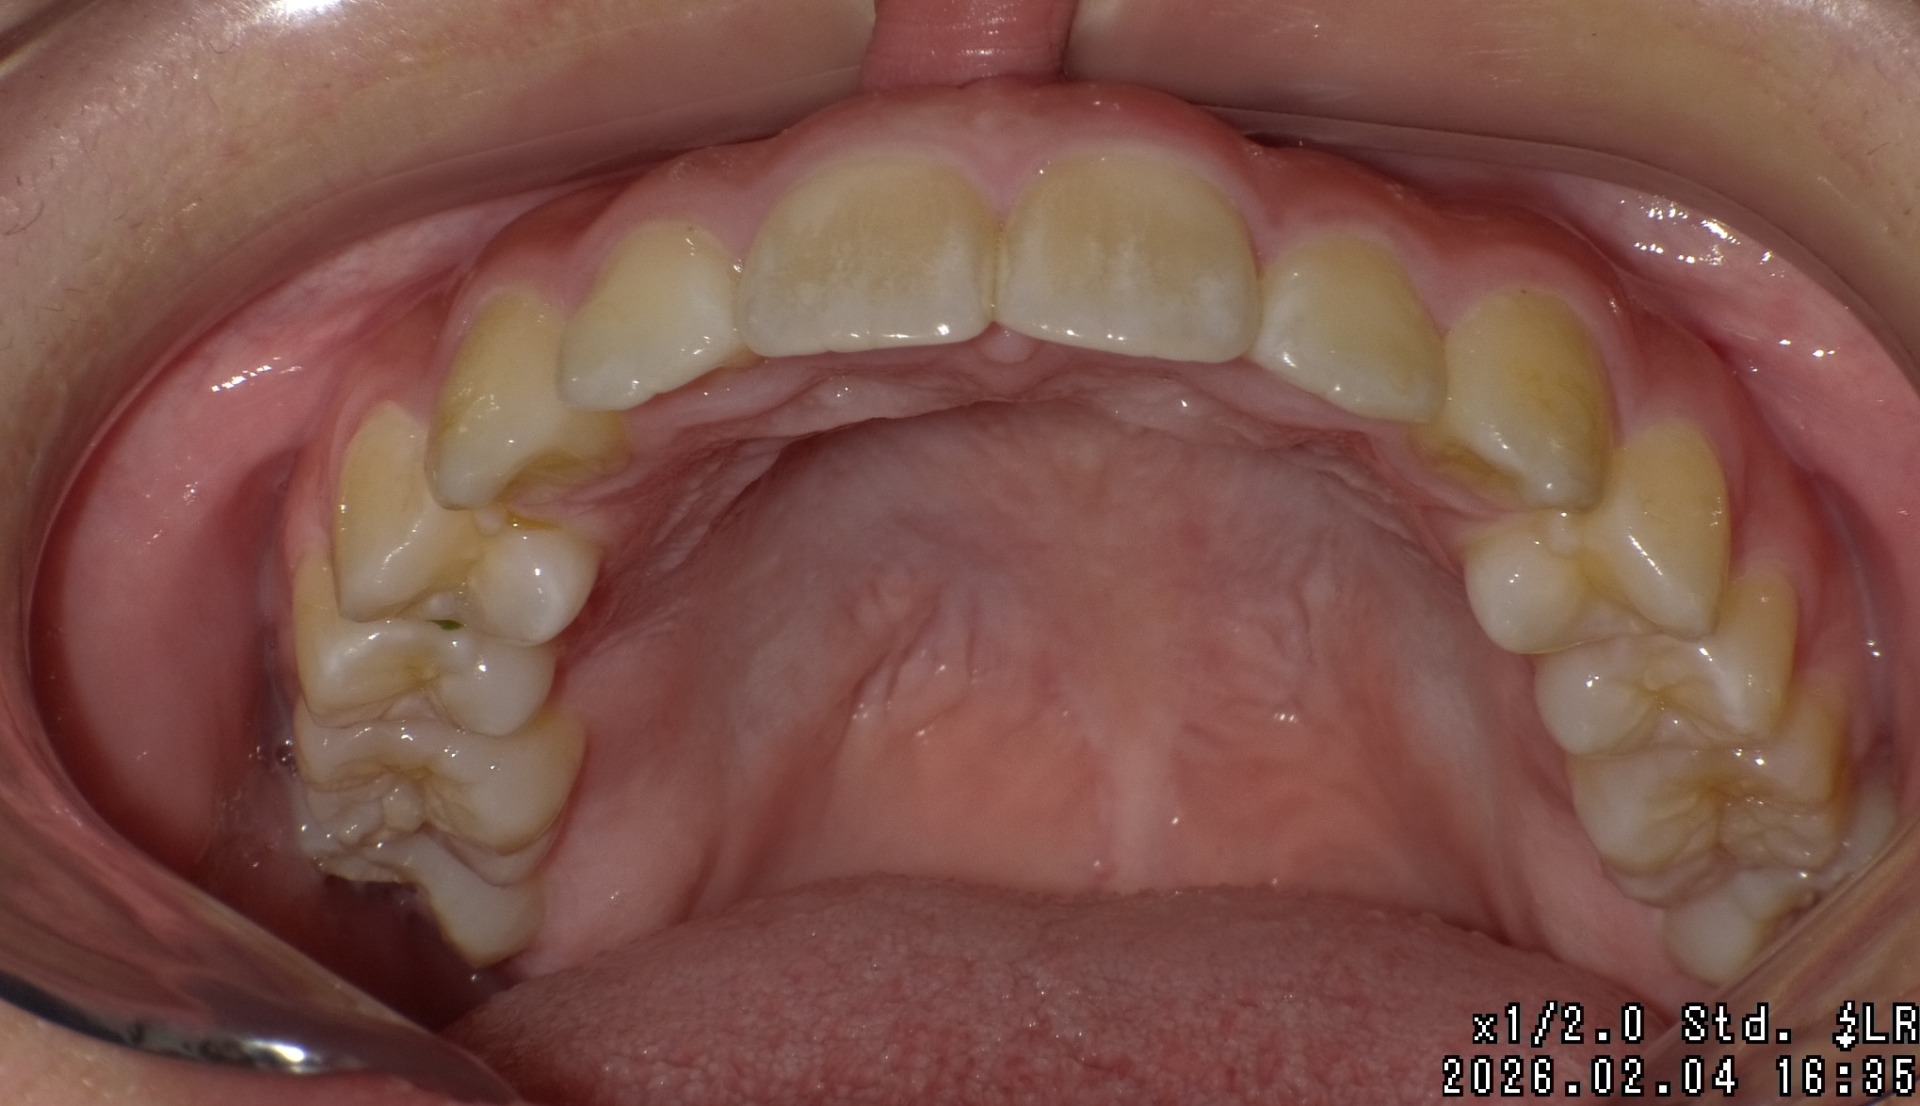

矯正前

| 症状 | 上顎前突 過蓋咬合 |

| 処置内容 | プレート拡大処置・ディスタライザー・インビザライン・オーソテイン・マルチブラケット装置 |